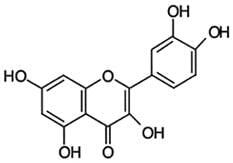

L'activité anticancéreuse de la quercétine a été largement étudiée. En 1989, un rapport a constaté qu'elle inhibait fortement la croissance de cellules de carcinome humain transplantées chez des rats immunocompétents16. Dans différentes expériences in vitro, la quercétine a montré des effets inhibiteurs de croissance de cellules de différents cancers humains : des cellules du côlon, du sein, de l'ovaire, gastro-intestinales ou leucémiques17.

Une activité anticancéreuse directe et une action synergique avec différents médicaments anticancéreux ont été attribuées à la capacité de la quercétine à inhiber la protéine kinase C18.

| Biodisponibilité

L'activité biologique de la quercétine dépend de sa biodisponibilité qui varie largement en fonction des sources dont elle est extraite ou, plus précisément, selon les caractéristiques de la chaîne sucrée de sa molécule. Des chercheurs hollandais ont comparé la biodisponibilité de quercétine provenant d'oignons et de thé.

Dans cette étude on a demandé à neuf sujets de suivre une alimentation sans quercétine pendant douze jours et on leur a donné les quatrième, huitième et douzième jours un supplément d'oignons frits (riches en glucosides de quercétine équivalents à 89 mg de quercétine) ou du thé (riche en rutinoside de quercétine équivalent à 100 mg de quercétine) ou 100 mg de quercétine. Les chercheurs ont constaté que l'absorption des glycosides de quercétine était de 52 %, celle du rutinoside de quercétine de 17 % et celle de l'aglycone de quercétine de 24 %21.

Une autre étude a comparé chez le cochon la biodisponibilité de différents glycosides de quercétine (dont l'isoquercitrine) et de l'aglycone de quercétine. Les résultats ont montré que l'isoquercitrine avait une biodisponibilité très supérieure à celles des autres formes.

Cette biodisponibilité était également dépendante de facteurs alimentaires. Ainsi, la consommation de viande stimulait son absorption de façon significative22.